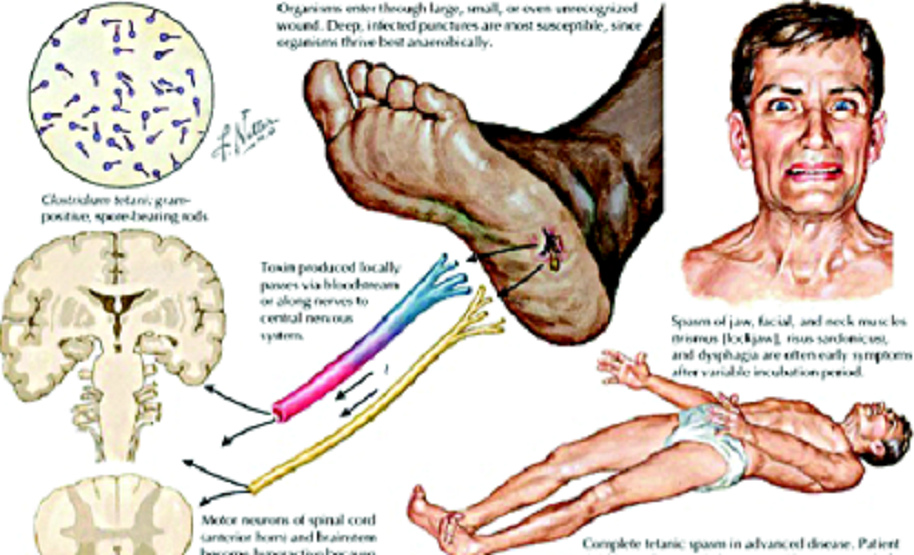

The healing of tetanus with Albert

Schweitzer

Child with tetanus muscle cramps, photo of the vaccine

toxic WHO [10] - circulation with tetanus, scheme

(English) [11]

Lambarene - June 1925: Tetanus does not cure - a

patient dies

(Letters from Lambarene, p.599)